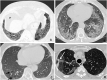

Rheumatoid arthritis (RA) is a systemic inflammatory disease, which primarily causes symmetric polyarthritis. An extrarticolar involvement is common, and the commonly involved organ is lungs. Although cardiac disease is responsible for most RA-related deaths, pulmonary disease is also a major contributor, accounting for ~10-20% of all mortality. Pulmonary disease is a common (60-80% of patients with RA) extra-articular complication of RA. Optimal screening, diagnostic, and treatment strategies of pulmonary disease remain uncertain, which have been the focus of an ongoing investigation. Clinicians should regularly assess patients with RA for the signs and symptoms of pulmonary disease and, reciprocally, consider RA and other connective tissue diseases when evaluating a patient with pulmonary disease of an unknown etiology. RA directly affects all anatomic compartments of the thorax, including the lung parenchyma, large and small airways, pleura, and less commonly vessels. In addition, pulmonary infection and drug-induced lung disease associated with immunosuppressive agents used for the treatment of RA may occur.